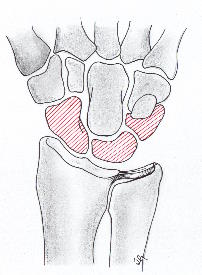

Lunate 의 sclerosis가 발견되면 Stage II 이며 Joint leveling 이 핵심입니다. ulna 변위가 중립 혹은 양성인 경우에는 radial wedge osteotomy나 그 외의 치료를 시행해 볼 수 있습니다.

Stage III 부터는 주상골도 영향을 받기 시작하며 회전을 하거나(IIIA, cortical ring 관찰가능), carpal height 가 줄어드는 것을 확인할 수 있습니다. (IIIB), IIIA 까지는 II와 치료를 거의 동일하게 하지만, IIIB 부터는 Proximal row carpectomy 나 STT, SC fusion 등을 시행해 볼 수 있습니다.

치료 중에 IIIB 부터 시행하는 치료는 아래와 같습니다.